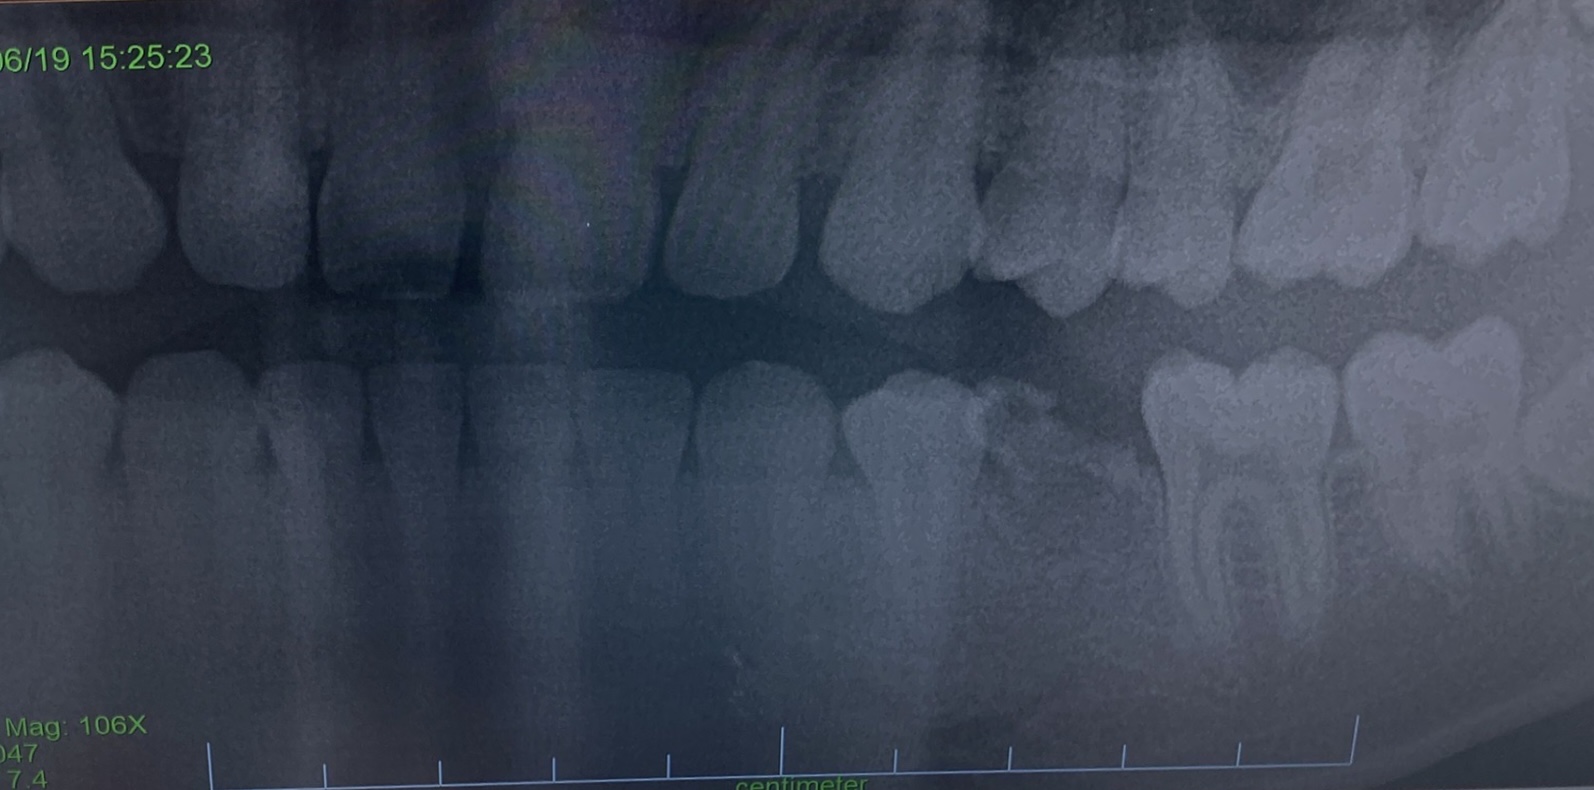

右下5番(添付写真)が先天性欠如歯で乳歯から永久歯に生え変わらず、乳歯が虫歯になっていたこともあり、先日抜歯しました。

画像1IMG_3228.jpg

向かって右側に写っていますから、右下5番ではなく、左下5番が先天性欠如しているのですね。